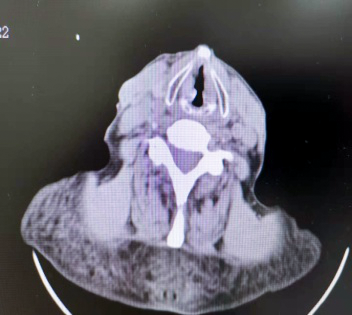

之后老人来到西安高新医院耳鼻喉科就诊,颈部 CT 检查提示:「右侧声带新生物」。

在充分评估支气管镜检查风险后,医生在局麻下为老者实施了电子支气管镜检查:右侧声带前中 1/3 可见肿瘤组织致喉狭窄。术后行活检组织病理证实为「高分化鳞癌」。